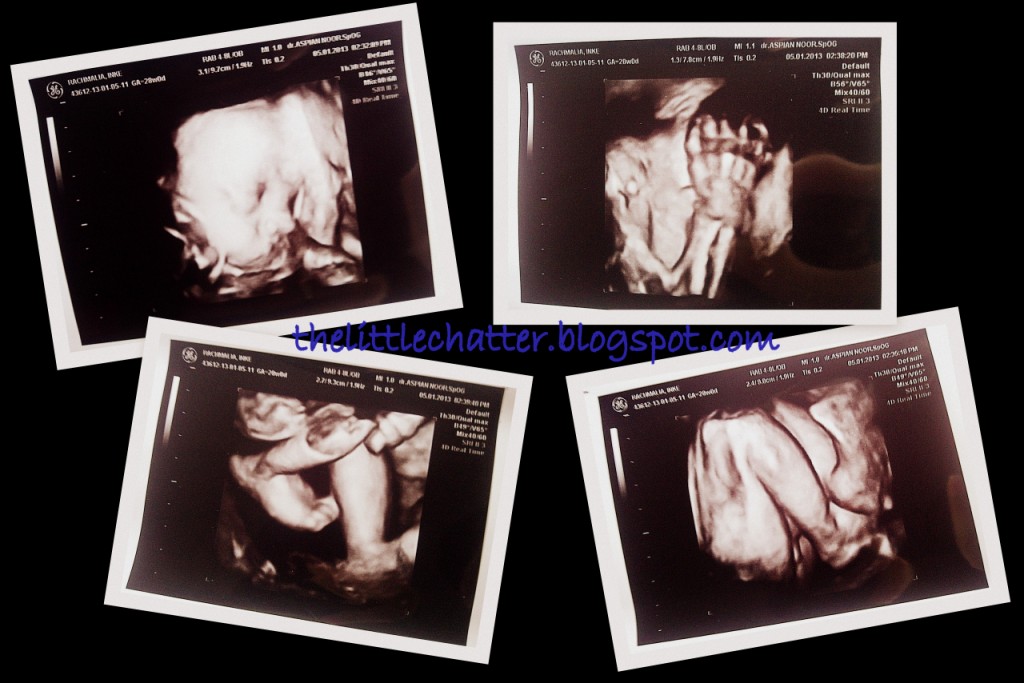

Gw kan minta di-cek kelamin baby en di-print-in dengan alesan selama ini biar setiap dokter yang periksa bilang I'm having a baby boy tapi gw gak pernah bisa ngerti en liat dengan jelas kelaminnya *si emak penasaran soalnya pas USG 4D juga dikekep di selangkangan ma si bocah walo keliatan sih bagian bawahnya dikit.. kelaminnya selalu cuma dikasih liat jelas ma si bocah pas USG 2D padahal emaknya gak ngerti liatnya*..

Sama Dr. Stella di-review bener2 en disorot jelas gitu kelamin si bocah, haha.. *Walo setelah keluar ruangan gw lupa lagi yang mana bagian apa*

Udah itu tanpa diminta muka si bocah di USG 4D aja loohh, diprint pula walo printnya versi 2D.. *check up yang terakhir2 cuma dpt print ukuran kepala n tulang paha n penjelasan ukuran2 bocah soalnya*

Based on last check up si bocah udah 1.6kg, posisi kepala udah dibawah *emang gak pernah pindah kayanya abis tiap check up posisinya di bawah terus, Alhamdulillah sih*, posisi placenta bagus, tali pusat ada di sela2 kaki *waktu pas USG 4D sempet bikin was2 karena posisi tali pusatnya lewat di bawah dagu, takut lehernya kelilit*, air ketuban cukup..